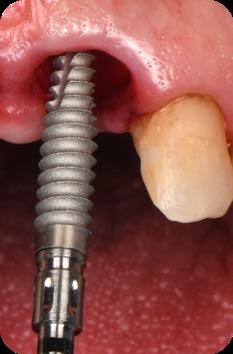

BioHorizons has introduced a new implant system that combines the advanced thread design of the Tapered Pro with the precision and stability of the Conelog conical connection. This integration delivers enhanced surgical handling, improved primary stability, and long-term biological benefits, supporting better patient outcomes in both aesthetic and functional zones.

This case was performed by Dr Homa Zadeh, DDS, PhD, a respected leader in periodontology and implant dentistry. Dr Zadeh’s approach emphasizes biologically driven protocols and evidence-based techniques, making this case a strong example of clinical excellence using the Tapered Pro Conical system. It involves the replacement of two front anterior teeth after they fractured off and the full restoration process.

Fig 1. Patient anterior situation. Two anterior crowns fractured off.

Fig 2. Intraoral radiograph indicating tooth structural loss extent.

Fig 5. Central incisors extracted using minimally invasive protocol. Alveolar bone and gingival tissues were intact after extraction

Fig 6. BioHorizons Tapered Pro Conical implants of 3.8 x 15mm placed according to the plan.

Fig 7. Implants immediately after installation.